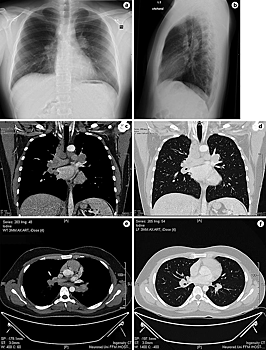

Зачастую заражённый коронавирусом и пневмонией направляют на КТ (компьютерную томографию). Также её назначают, когда при нормальных результатах рентгена лёгких у человека всё равно есть такие симптомы, как сильный кашель, одышка, падение уровня кислорода в крови. Во время процедуры лёгкие сканируются послойно. То есть изображение в итоге получается объёмным, что позволяет точнее поставить диагноз.

Рентген, продолжает медик, иногда может показать нормальное состояние ткани лёгких, а на КТ будут видны в этом же месте изменения.